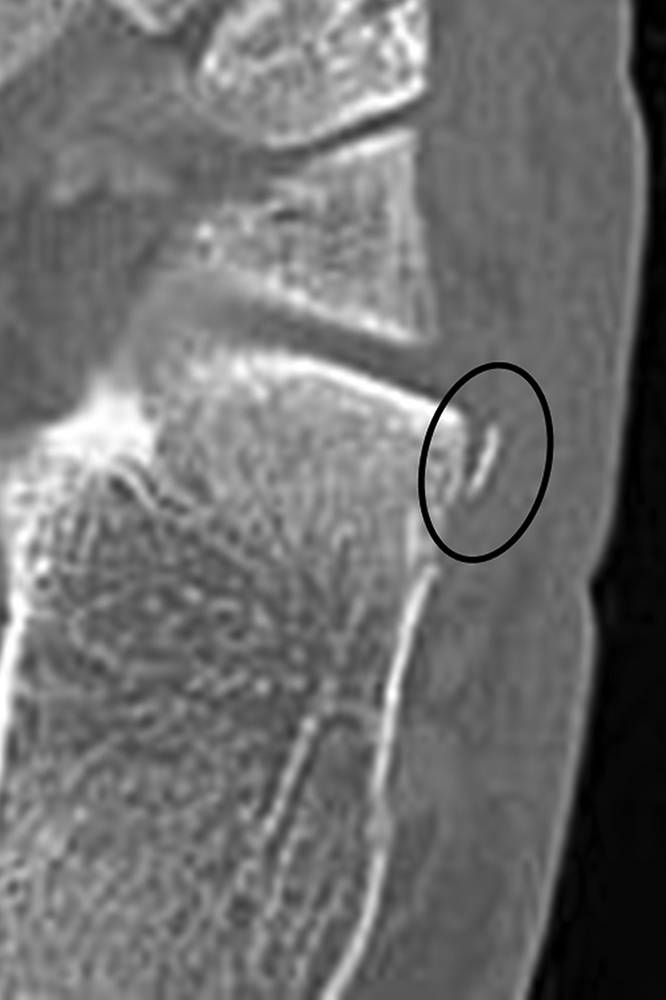

图10B- CT图像显示撕脱性骨折(椭圆形)对应于背侧跟骨韧带的近端附着。